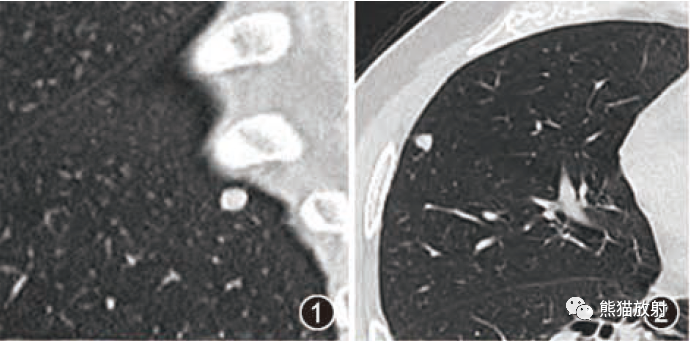

CTA—囊状动脉瘤表现为起自动脉的囊袋状突起,有蒂(瘤颈)与载瘤动脉相连,轮廓清晰;梭形动脉瘤表现为血管不规则迂曲扩张,无瘤颈。